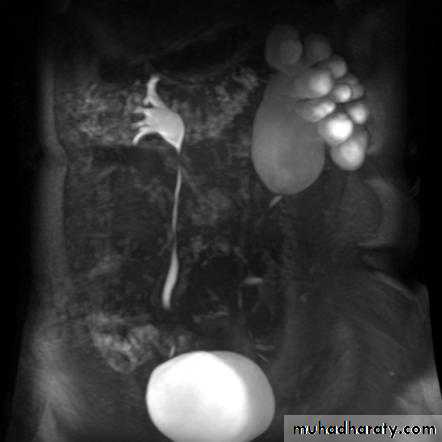

ADPKD:

• Familial disorder

• Age (35-55 years)

• Presented with HTN, renal failure and hematuria.

• Bilateral disease.

• Cysts may also be seen in other organs like liver and pancreas .